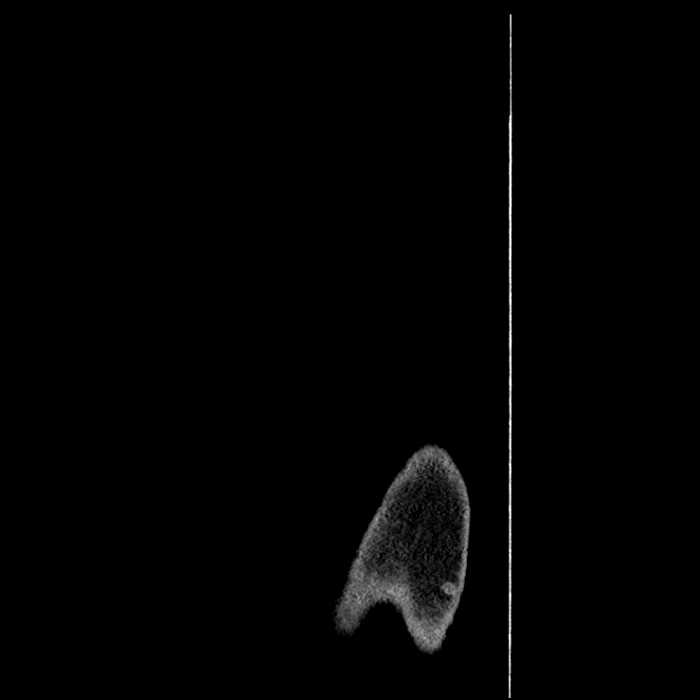

• Incidental splenule

• Circumscribed sclerotic lesion in the left anterolateral seventh rib without aggressive features, likely a bone island

Hepatic abscess showing the double target sign with low density internally surrounded by a thin inner enhancing rim (red arrow) and ill-defined outer low density rim (yellow arrow). Blue arrow indicates an internal septation. Red arrows: additional smaller subcapsular abscesses. Red arrow: focal contained perforation associated with diverticulitis.